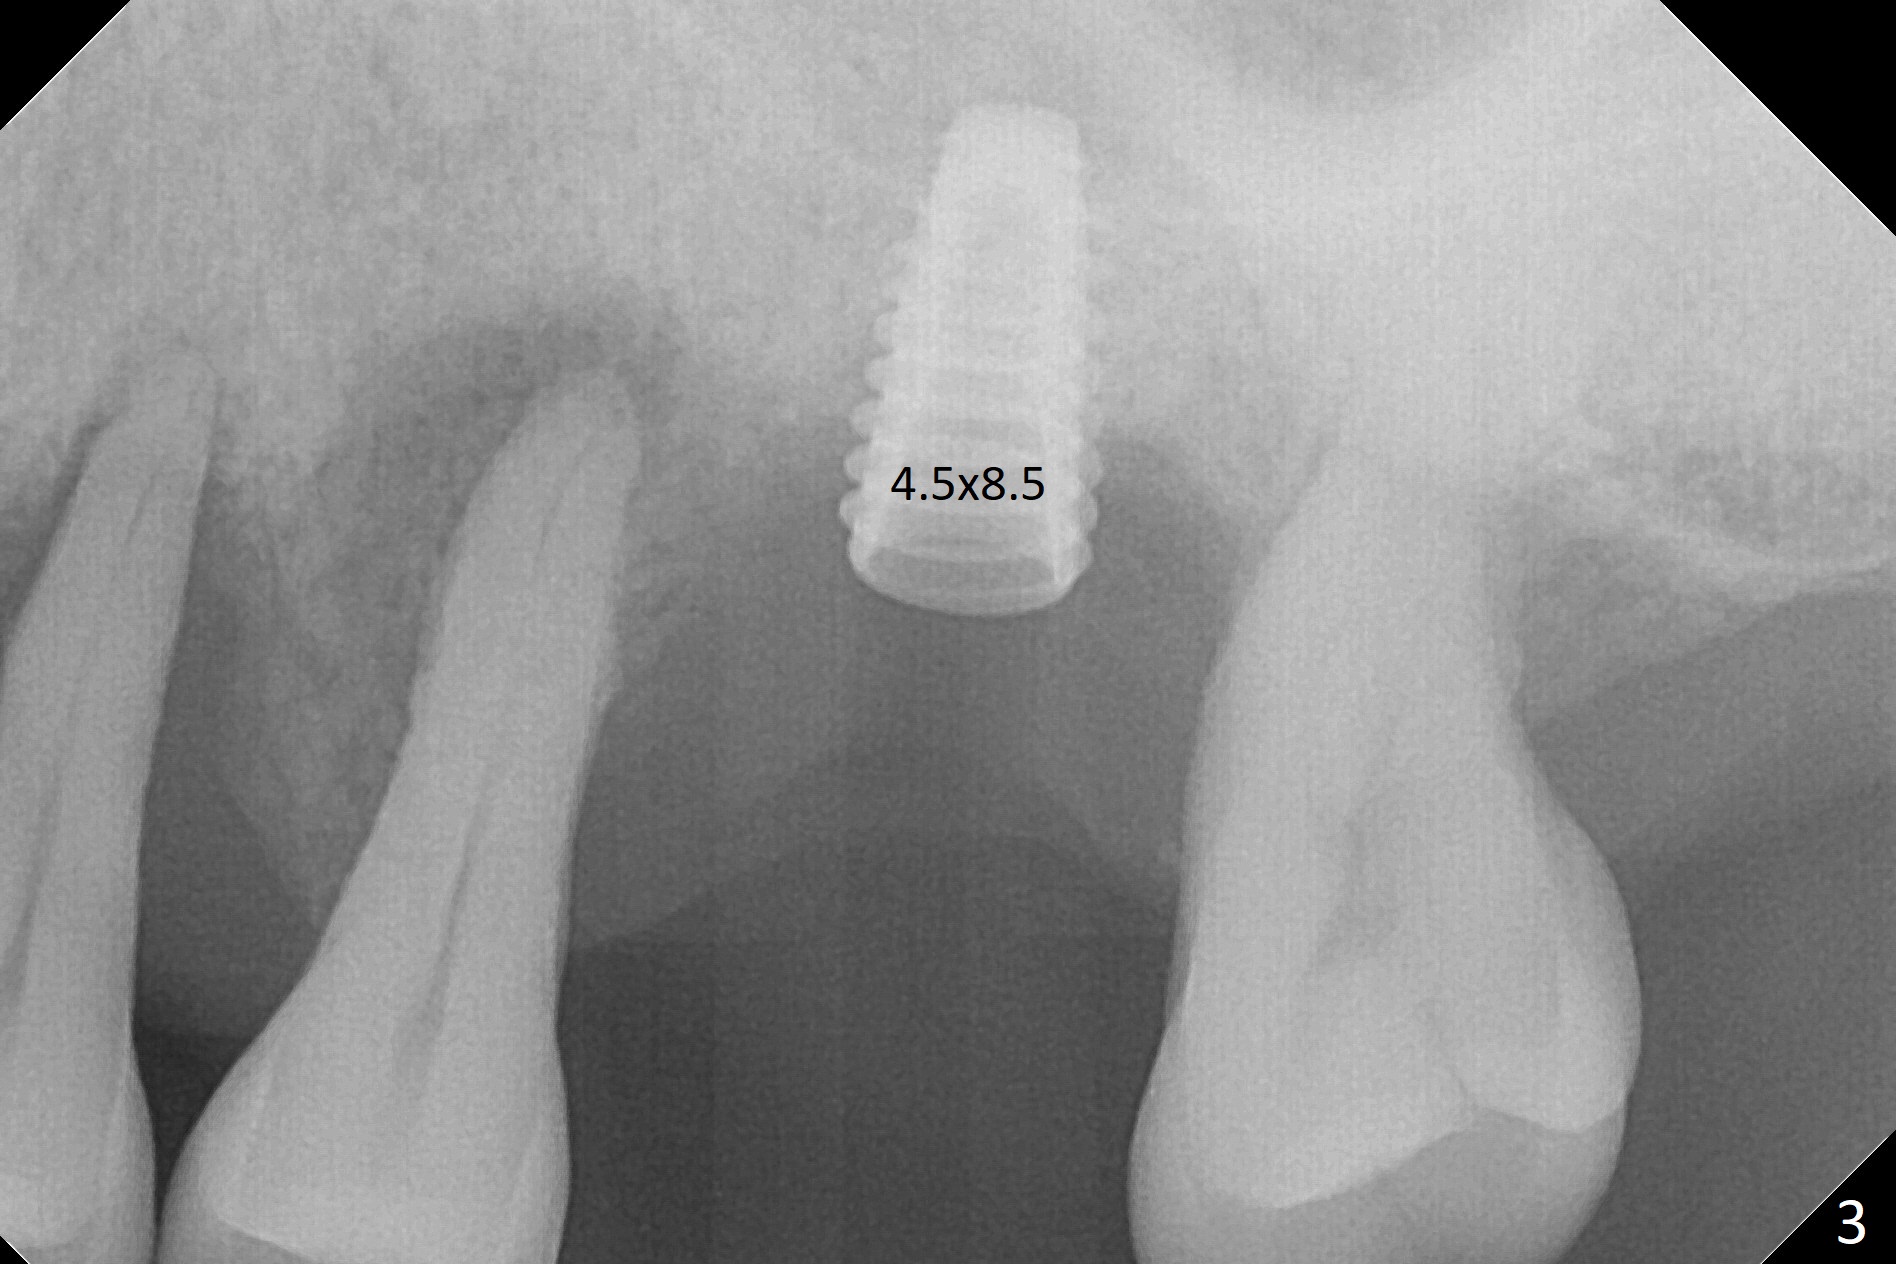

Bone height at #14 two months post exfoliation is ~ 4 mm (Fig.1). Bone expansion is difficult because of dense bone. After drilling, a 4.5 mm tap is inserted with stability (Fig.2). Sinus lift is accomplished with RT3 and autogenous bone prior to placement of a 4.5x8.5 mm implant (Fig.3). Because of flapless surgery and tight and long gingiva, bone graft around the coronal end of the implant is intentionally not placed. A 5.5x5(4) mm abutment is immediately placed for an immediate provisional. (Fig.4). Take PA and impression when the patient returns. The provisional dislodges 3.5 months postop (Fig.4); impression is taken. The patient reports hot sensitivity and pain after meal at the implant site (Fig.5). After removal of the implant crown/abutment, she feels better. If not, it seems necessary to extract the tooth #13 for a 13 mm long implant with a mill abutment (Fig.6).